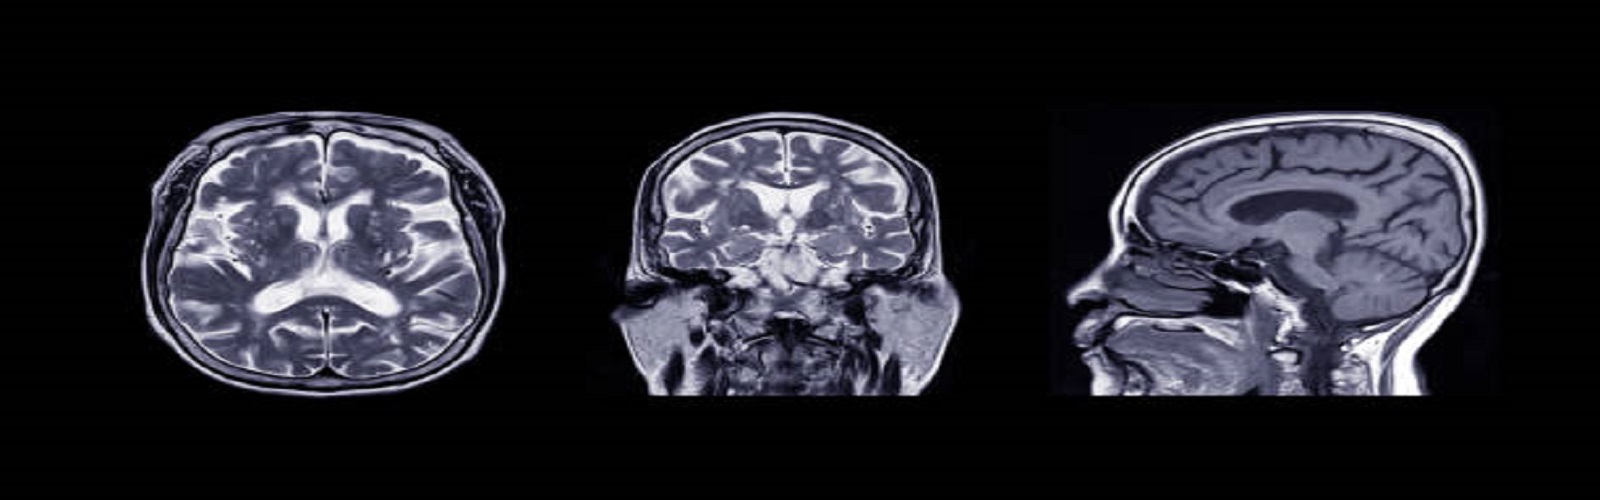

1. Tripathi, A., Jose Guerrero Gonzalez, Traci Snedden, Alison Brooks, Peter Ferrazzano, Christian Franck, Rika Carlsen, 2022. Effect of Individual Anatomical Differences in Brain Deformation From Head Accelerations: A Computational Study. International Mechanical Engineering Congress and Exposition, ASME, Columbus, Ohio, USA.

2. Tripathi, A., Alison Brooks, Christian Franck, Rika Carlsen, 2022. Pediatric traumatic brain injury (pTBI) in soccer headers: A computational study. BioS Seminar, University of Wisconsin Madison, Madison, Wisconsin, USA. (Online).

4. Tripathi, A., Alison Brooks, Christian Franck, Rika Carlsen, 2021. Purposeful Heading in Youth Soccer. Orthopedic Grand Rounds, University of Wisconsin Madison, Madison, Wisconsin, USA. (Online).

1. Tripathi, A., Jose Guerrero Gonzalez, Traci Snedden, Alison Brooks, Peter Ferrazzano, Christian Franck, Rika Carlsen, 2022. Effect of Individual Anatomical Differences in Brain Deformation From Head Accelerations: A Computational Study. PANTHER Meeting. University of Wisconsin Madison, Madison, Wisconsin, USA.